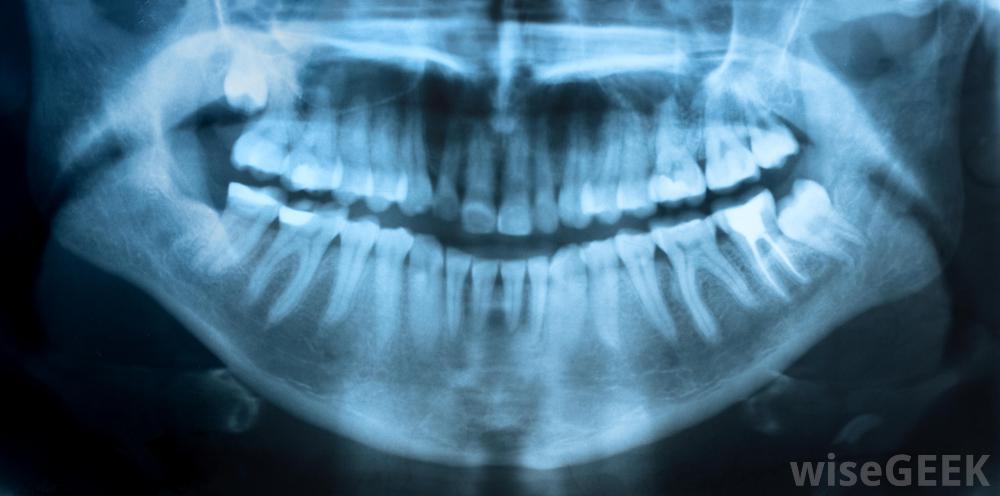

如果你正在經歷補牙的疼痛,你需要考慮一下最近你在牙齒里植入了填充物。新的填充物可能需要一段時間的調整,因此,你可以使用非處方藥或局部止痛藥來緩解你的不適,直到你的口腔痊愈,你習慣了新的牙科工作。另一方面,牙齒填充物疼痛可能是你的填充物之一已經開裂或移動,開始腐爛的跡象。疼痛也可能是填充物放置不當的跡象,所以最好是聯系你的牙醫,安排一個預約,讓他或她檢查你的牙齒,找出你疼痛的原因。各種治療方法從使用非處方止痛藥到更換充填物到嚴重受損牙齒的根管殘牙是充填后牙痛的一個原因。當你填滿牙洞后,你的牙醫可能會告訴你,你的牙齒可能會有一段時間的敏感。雖然這種敏感通常是暫時的,但它會讓你感到不舒服,所以在治療之后,你可以做一些事情來解決牙齒填充物的疼痛問題。首先你要做的是避免食物和行為引起敏感。對很多人來說,非常熱或非常冷的食物和飲料,以及一些糖果,都會引發牙齒和牙齒填充物的疼痛。避免這些食物和飲料,以防幾周后,你的嘴就會習慣這種填充物。市面上有各種各樣的牙膏是為敏感牙齒而配制的,經常使用它們可以大大降低牙齒的敏感性和不適感牙齒感染會導致疼痛。如果您發現您的牙齒在接受補牙后的幾周內仍然敏感,或者您在一段時間前補牙后開始感到疼痛,請聯系您的牙醫。你的牙醫可以檢查你的牙齒并要求進行x光檢查,以幫助他或她了解什么可能導致你的牙痛。如果發現感染,他或她可能會開抗生素,你可以討論各種治療牙齒的方法。你的牙醫可能會幫你更換填充物,把牙冠放在牙齒上,或者,如果有必要,建議做根管治療很重要,由于齲齒通常是漸進性的,可能會對牙齒和口腔造成嚴重損害,甚至可能導致身體其他部位的疾病。如果有人在應用填充物時,應咨詢牙醫。可能需要x光片來確定牙齒受傷的原因患者在填充后可能會感到牙痛。